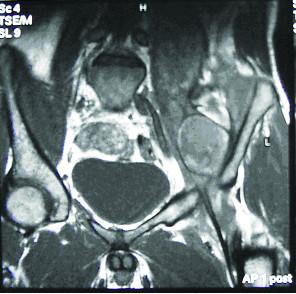

Iliopsoas pseudotumour is a serious complication of haemophilia. We present the case of a 20-year-old male patient with a six-month history of left leg weakness, limitation of movement and wasting of the muscles. Clinically he was diagnosed as having a psoas muscle rhabdomyosarcoma. During a computed tomography (CT) scan-guided Tru-cut biopsy he developed a serious and life-threatening bleeding from a retroperitoneal muscular haematoma. The patient underwent laparotomy prior to his final diagnosis of an Iliopsoas pseudotumour, which is a serious, as well as rare, complication of haemophilia.

髂腰肌假瘤是血友病的一种严重并发症。我们报告一例20岁男性患者,有六个月左腿无力、活动受限及肌肉萎缩病史。临床上他被诊断为腰大肌横纹肌肉瘤。在计算机断层扫描(CT)引导下进行粗针穿刺活检时,他因腹膜后肌肉血肿出现了严重的、危及生命的出血。在最终诊断为髂腰肌假瘤之前,患者接受了剖腹手术,髂腰肌假瘤是血友病一种严重且罕见的并发症。